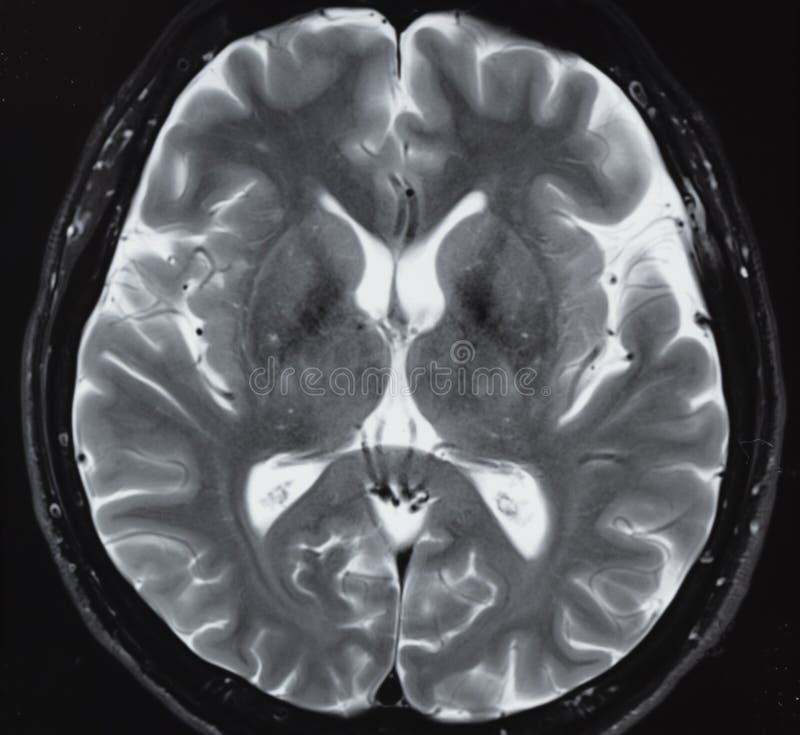

Lista muestra hermosas imágenes de resonancia magnética cerebral normal y anormal dinosenglish.edu.vn para que puedas explorar más en detalle.

resonancia magnética cerebral normal y anormal Pin en NEUROCIENCIAS resonancia magnética de cerebro Resonancia magnética (RM) de cerebro, corte axial ponderado en T2: la … VIDEO Nueva mancha en la Resonancia

Engineer Team : RESONANCIA MAGNETICA Magnetic Resonance Imaging – Clinical Images Hallazgos por resonancia magnética cerebral de nuestro paciente. M, 21 … Imágenes por resonancia magnética anormales como predictoras de mal … Imágenes por resonancia magnética anormales como predictoras de mal … Lesiones en resonancia magnética (RM) del encéfalo y la médula espinal … Pin en Resonancia Magnética del Encéfalo A) Resonancia magnética cerebral (RMC) mostrando infartos en … Caso 1: Edema cerebral visualizado mediante RM. (A) Secuencia T1 plano … Rascacielos dormir pasta tac y resonancia diferencias retrasar … Pin on Apuntes de Enfermería y T.C.A.E Resonancia magnética cerebral secuencia T2, que muestra lesión … Meningitis aguda en la enfermedad de Behçet | Reumatología Clínica Resonancia magnética coronal normal del cerebro Fotografía de stock – Alamy Imágenes de resonancia magnética, la imagen de la cabeza en diferentes … Resonancia magnética cerebral A) protocolo T1 sagital (Caso 1). Se … Resonancia magnética cerebral. Secuencia T1 corte sagital. Atrofia … Resonancia magnética de cerebro, cortes axiales, secuencias T2. Señal … Resonancia magnética de cráneo. A y B) Cortes axiales FLAIR … Resonancia magnética (RM) de cerebro, corte axial ponderado en T2: la … RM cerebral: Interpretación paso a paso | Kenhub Resonancia magnética de cerebro, cortes axiales, secuencias T2. Señal … De Resonancia Magnética De Cerebro Foto de archivo – Imagen de arteria … Top 107+ Imagenes de resonancia cerebral normal – Destinomexico.mx -Imagen por resonancia magnética del cerebro. a) Cortes sagital y axial … resonanCia magnétiCa Cerebral donde se observa hiperintensidad a nivel … MRI (Imagen de resonancia magnética) – Tomografía computarizada de la … Meningioma – NCI Imágenes por resonancia magnética coloreadas del cerebro sano del … Resonancia magnética cerebral en secuencia FLAIR, que muestra lesiones … Contraste resonancia magnetica cerebral – senturinthegreen Relación de los espacios de Virchow-Robin con la enfermedad de … Gliomatosis cerebral – Instituto Nacional del Cáncer Pin en Neurology. Recomendaciones para la utilización e interpretación de los estudios de … Fotografía De La Proyección De Imagen De Resonancia Magnética Del … atmósfera Dirigir Cumplir anatomia resonancia magnetica Desarrollar … Pin en #MEDICINA,#SALUD Resonancia magnética de la nasofaringe De Resonancia Magnética De Cerebro Foto de archivo – Imagen de polilla … Atrofia cortical global de predominio parietal en la Resonancia … Resonancia magnética cerebral | Download Scientific Diagram Neuroblog: Resonancia magnética cerebral en la trombosis crónica de … De Resonancia Magnética De Cerebro Imagen de archivo – Imagen de … ¿Cuáles son los riesgos de la resonancia magnética? – Integra Salud … Resonancia magnética cerebral al decimocuarto día de ingreso: área … Resonancia magnética. Corte axial mostrando área infartada en el … Resonancia magnética cerebral del paciente AV evidenciando lesiones en … -Ressonância magnética de encéfalo mostrando múltiplas imagens … Resonancia magnética cerebral secuencia FLAIR (Fluid Attenuated … Resonancia magnética cerebral con protocolo de epilepsia, en sección … Resonancia magnética cerebral en corte sagital. Se observa una evidente … Resonancia magnética craneal en la que se evidencian lesiones … Logran visualizar el cerebro a detalle más completo tras una resonancia … Así decide el cerebro la severidad de un castigo De Resonancia Magnética De Cerebro, Imagen de archivo – Imagen de … A) Resonancia magnética cerebral; Secuencia Tof: oclusión de arteria … Un estudio asocia la ansiedad con la aparición rápida del Alzheimer IMÁGENES DE 18 F-PR04.MZ PET FUSIONADA CON RESONANCIA MAGNÉTICA … Imágenes por resonancia magnética anormales como predictoras de mal … Tumores de la región pineal – Instituto Nacional del Cáncer Epilepsia: una historia de voces y fantasmas | Neurología Contribución de las imágenes de resonancia magnética por tensor de … Resonancia magnética secuencia T2 plano coronal de quiste epidermoide … Resonancia Magnética Cerebral del paciente: a. Aumento de… | Download … Resonancia magnética cerebral 2022 Síndrome de hemiconvulsión-hemiplejía-epilepsia. Seguimiento de un caso … Enfoque Radiologico: La resonancia magnética permite detectar lesiones … Resonancia magnética craneal T1 con contraste que muestra angiomatosis … guidewiz – Blog Resonancia magnética cerebral, secuencia SWI. Ribete hipointenso en la … resonAnCiA mAgnétiCA de ColumnA Con gAdolinio. Corte sAgitAl en t1 de … SEMANA 12: FUNDAMENTOS DE RESONANCIA MAGNÉTICA NUCLEAR. INDICACIONES Y … DIAGNÓSTICO DE ESCLEROSIS MÚLTIP Magnetic resonance imaging of the brain – Alchetron, the free social … Resonancia magnética de órbitas | Instituto Radiológico Dr. E Castillo Alteración de la marcha en un paciente post-trasplante hepático Resonancia magnética cerebral de un paciente sano (Ay B) y paciente que … Utilidad de la resonancia magnética craneal para el diagnóstico de la … Resonancia Magnética Del Cerebro El Tumor Cerebral Foto de stock y más … De Resonancia Magnética De Cerebro Imagen de archivo – Imagen de … ABDALLA RADIOLOGIA: NEURINOMA ACUSTICO Atrofia cortical global de predominio parietal en la Resonancia … Resonancia Magnética : Producción de la imagen MRI Brain Scan — Stock Photo © Bunyos30 #18724051 Mri (imagen de resonancia magnética) Monitor con imagen de captura de … Tomografía computarizada vs resonancia magnética: diferencia y … Tumores Cerebrales – Unidad de Neurocirugía RGS Resonancia magnética de la columna, sección sagital. Observe los discos … La resonancia magnética, una técnica imprescindible en el diagnóstico … Perfusión Cerebral por Resonancia Magnética | ¿Qué es? ¿Necesita Contraste? Resonancia Magnética Cerebro A: resonancia magnética, T2 coronal preoperatoria; se observa lesión en … Resonancia magnética cerebral — Foto de stock © Bunyos30 #27340623 La resonancia magnética se perfila como detector de mentiras | Futuro … Resonancia magnética cerebral en T1 con gadolinio, cortes axial (a … MRI brain : show brain tumor at right parietal lobe of cerebrum — Stock … NEUROIMÁGENES EN ENFERMEDAD DE PARKINSON: ROL DE LA RESONANCIA …